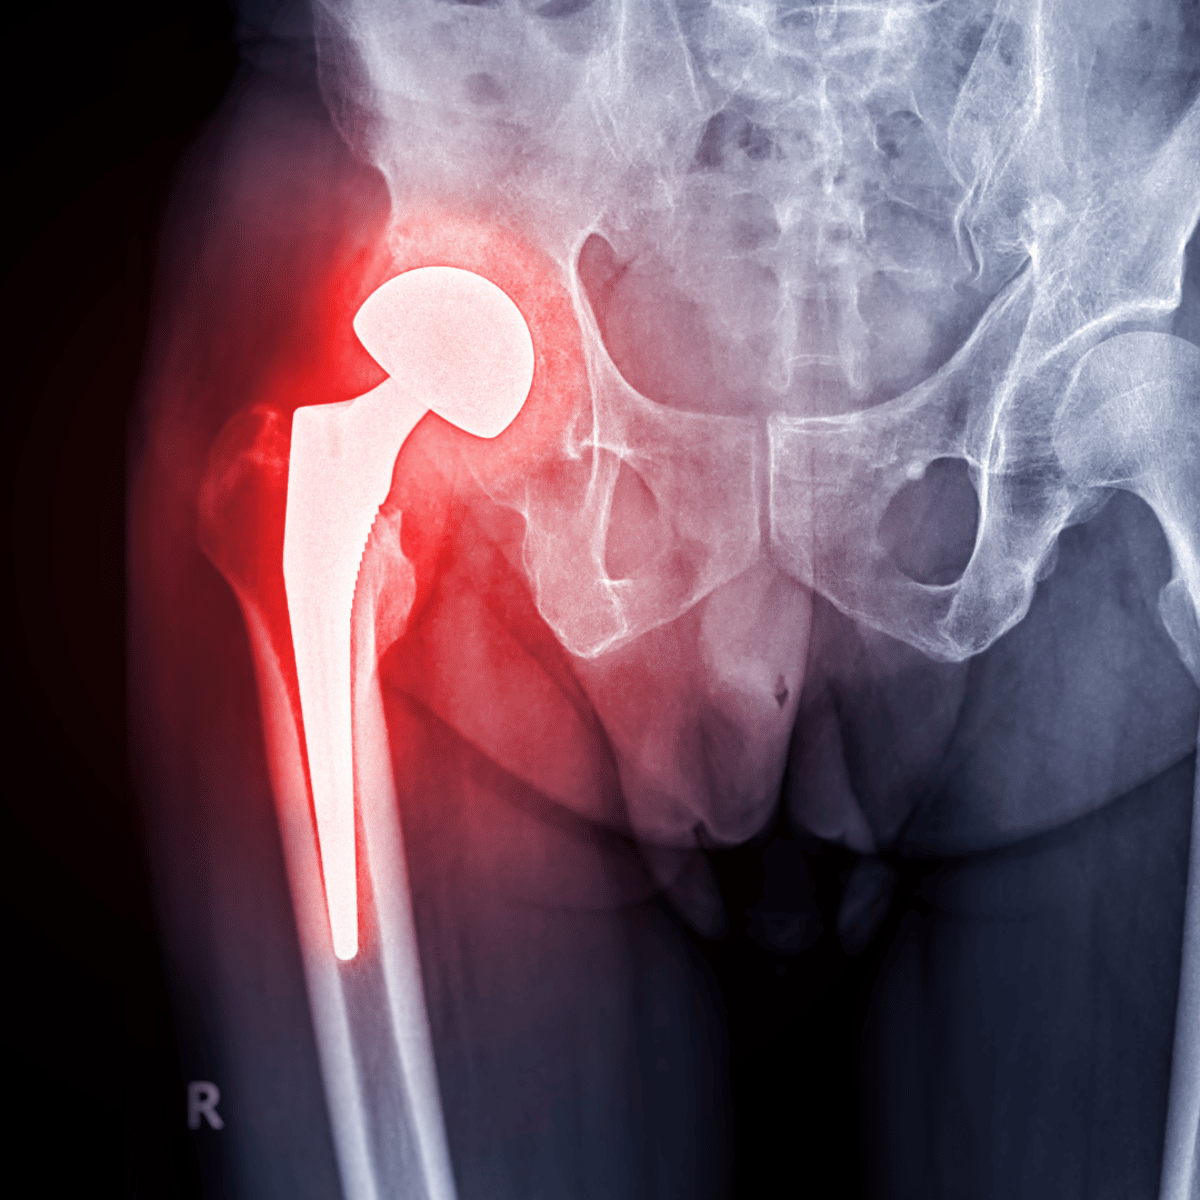

Hip resurfacing is a bone-conserving alternative to total hip replacement, especially suited for younger, active patients. As advancements continue, several innovative techniques and technologies are expected to improve the effectiveness and safety of this procedure by 2025.

All-Ceramic Hip Resurfacing Implants

A significant innovation in hip resurfacing is the development of all-ceramic systems. These implants aim to reduce complications associated with metal implants, such as metallosis, while offering improved biocompatibility and durability. This development represents a breakthrough for patients seeking long-lasting and safer options. -

Patient-Specific Customization

New imaging techniques and 3D printing technologies allow the creation of implants tailored to an individual’s anatomy. Customization enhances the fit and alignment of the implants, resulting in better functionality, quicker recovery times, and improved overall outcomes. -

Advancements in Biomaterials

The use of advanced biomaterials, including highly durable polyethylene and innovative metal alloys, has improved implant longevity and reliability. These materials significantly reduce wear, decreasing the need for revision surgeries and increasing the procedure's success rate. -

Minimally Invasive Techniques

Minimally invasive surgical methods, characterized by smaller incisions and muscle-sparing approaches, have become more prevalent. These techniques reduce tissue disruption, allowing for shorter hospital stays, faster rehabilitation, and a quicker return to daily activities. -

Technological Integration

The incorporation of advanced technologies such as navigation systems, robotic-assisted surgery, and sensor-equipped implants is enhancing the precision of surgical procedures. These technologies assist in achieving optimal implant placement and provide valuable postoperative monitoring, improving long-term success rates. -

Metal-on-Polyethylene Hip Resurfacing

Recent developments in implant design, such as metal-on-polyethylene systems, offer alternatives to traditional metal-on-metal implants. These innovations reduce the risk of complications related to metal ion release, providing safer and more effective solutions for patients.

These advancements are transforming hip resurfacing, delivering improved outcomes through durable materials, personalized designs, and less invasive approaches. As a result, patients can expect more reliable, tailored, and recovery-friendly options in the coming years.